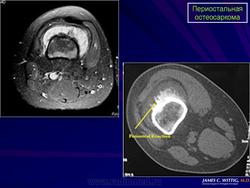

Рентгенологически обнаруживается преимущественно диафизарная локализация; прилежащий к опухоли кортикальный слой утолщен; костномозговой канала не вовлечён эндостальная поверхность кортикальной кости не изменена. Края минерализованной порции опухоли нерегулярной формы и иногда формируют радиально расположенные по отношению к оси кости, спикулы.

Рентгенологическая картина выявляет очаг поражения на поверхности кости. Очаговые фокусы кальциноза, формирование спикул, нечеткая граница опухолевого узла, мягкотканный компонент, отсутствие поражения медуллярного отдела кости, все названные рентгенологические признаки характерны для периостальной остеосаркомы. Для выявления характера поражения костномозгового канала проводится дополнительное исследование с применением КТ и МТР.